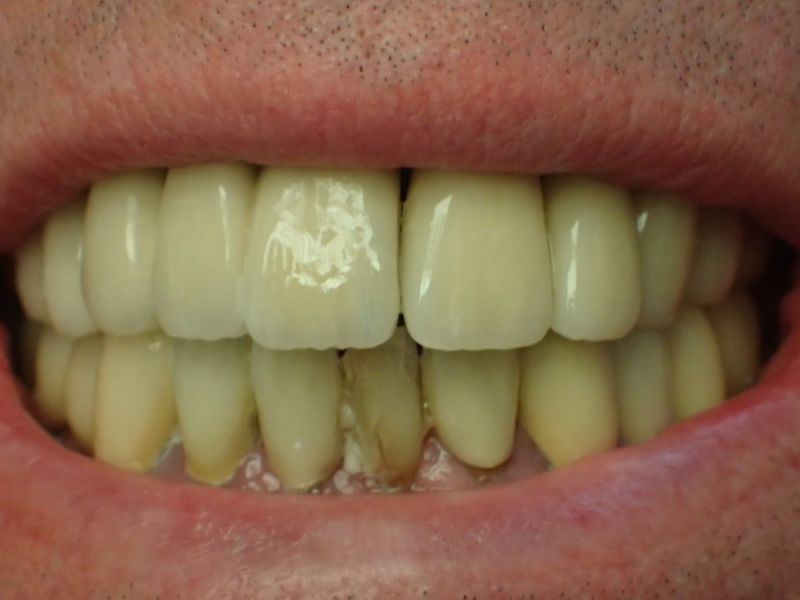

Kieler Patient erhält implantatgetragene Frontzahnbrücke

Dieser Patient fällt ein bißchen aus dem üblichen Rahmen, weil die vielfachen Versorgungen hier nicht zeigtlich im Rahmen einer CMD Behandlung erbracht wurden, sondern über viele Jahre hinweg nach und nach.

Der Patient wurde von dem Praxisvorgänger übernommen und befindet sich daher seit weit über 20 Jahren hier in Behandlung.

Dieser Patient hat keine funktionellen Beschwerden und aufgrund der geschilderten Vorgehensweise war es niemals Ziel der Behandlung die bestehenden Bissverhältnisse zu untersuchen, oder therapeutisch zu verändern, weil der Patient zu den Patienten gehört, die mit einem fehlerhaften Biss, wir nennen es Habituelle Okklusion, keinerlei Probleme und Beschwerden hat.

Was man an diesem Fall gut zu erkennen vermag, dass Patienten, die für sich irgendwann entschieden haben, nicht mit einem herausnehmbaren Zahnersatz ihren Lebensabend verbringen wollen auch nach und nach auf eine Implantatpfeilerstützzahl kommen, die genügend Substanz für die Lebensphase bieten, in der körpereigene Stützsubstanz, in Form von Zähnen zunehmend verloren geht.